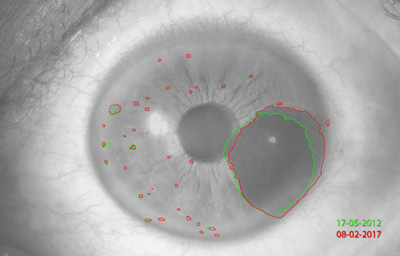

Melanocitomas

Melanocitoma es una lesión benigna, profundamente pigmentada, variante del, nevus uveal que fue originalmente descrito por Zimmerman y Garron en 1962 en el nervio óptico; ahora se sabe que puede aparecer en cualquier lugar del tracto uveal.

Son masas con algo de elevación, con pigmento marrón oscuro casi negro, frecuentemente con apariencia de “ montículo de arena negra”. Sus células son ovoides con núcleos uniformes, pequeños y muy pigmentados. pueden generar satélites en el estroma o en el ángulo de la cámara anterior. Pueden evolucionar a Melanoma (30)

Archivo Fotográfico Dr. Francisco Barraquer. 2012

Archivo Fotográfico Dr. Francisco Barraquer. 2017

Estudio comparativo